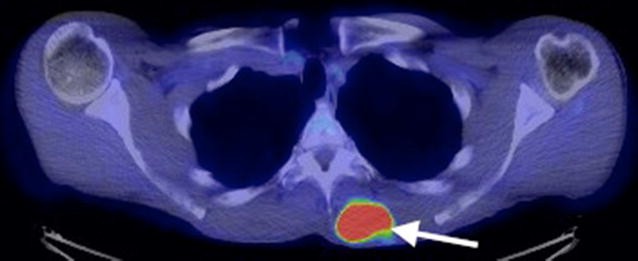

The patient completed a course of radiotherapy and, nine months later, a mobile soft tissue lump on his back was noted. A thoracic CT scan revealed a soft tissue lesion superficially located in the inferior portion of the left trapezius muscle. The lesion was lobulated, had a low attenuation centre, showed peripheral enhancement and did not exhibit evidence of matrix calcification (Fig. 4). The lesion increased in size and a subsequent MRI scan performed 6 months later confirmed the presence of a solid soft tissue mass up to 5 cm in diameter in the medial left trapezius muscle. The lesion indented the underlying paravertebral muscles but remained well-defined and did not invade the deeper musculature. The lesion returned isointense T1-W signal relative to skeletal muscle and heterogeneous high T2-W signal. There was no internal calcification, haemorrhage or cystic degeneration. Peripheral feeding vessels were present (Fig. 5). A PET-CT scan demonstrated that the intramuscular lesion was extremely FDG avid with an SUVmax of 22.1 (Fig. 6). PET-CT also revealed disseminated, markedly FDG avid metastases in liver, bone and pleura and residual meningioma in the right frontal lobe.

Radiological features of the chest wall tumour in our case were not specific; the diagnosis of a metastatic tumour was supported radiologically by the interval increase in the size of the lesion, as well as high FDG uptake and the finding of lesions at other sites on the PET-CT scan. Multiple deposits were also observed in other extracranial sites in previous reports of soft tissue metastasis from malignant meningioma [3, 4]. The tumour in the frontal lobe showed several radiological findings that have been described as potential markers of atypical or malignant meningiomas including indistinct or irregular tumour margins, marked peritumoral oedema, inhomogeneous enhancement post-contrast, intrinsic cyst-like areas, disruption of the arachnoid at the brain-tumour interface and adjacent bone destruction [18–24].

Knowledge of the clinical and radiological information was essential to establish the diagnosis of metastatic malignant meningioma in our case, particularly the previous history of anaplastic meningioma and the radiological identification of FDG avid lesions at several sites. Although very rare, the possibility of metastatic meningioma should be considered in the differential diagnosis of a malignant soft tissue tumour, where tumour cells strongly express EMA and other epithelial markers.